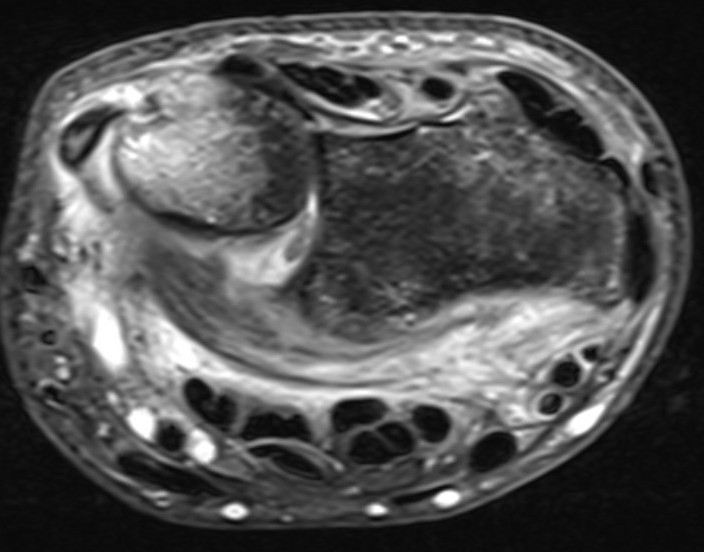

MRI

MRI demonstrating dorsal distal ulna subluxation associated with significant ligament disruption